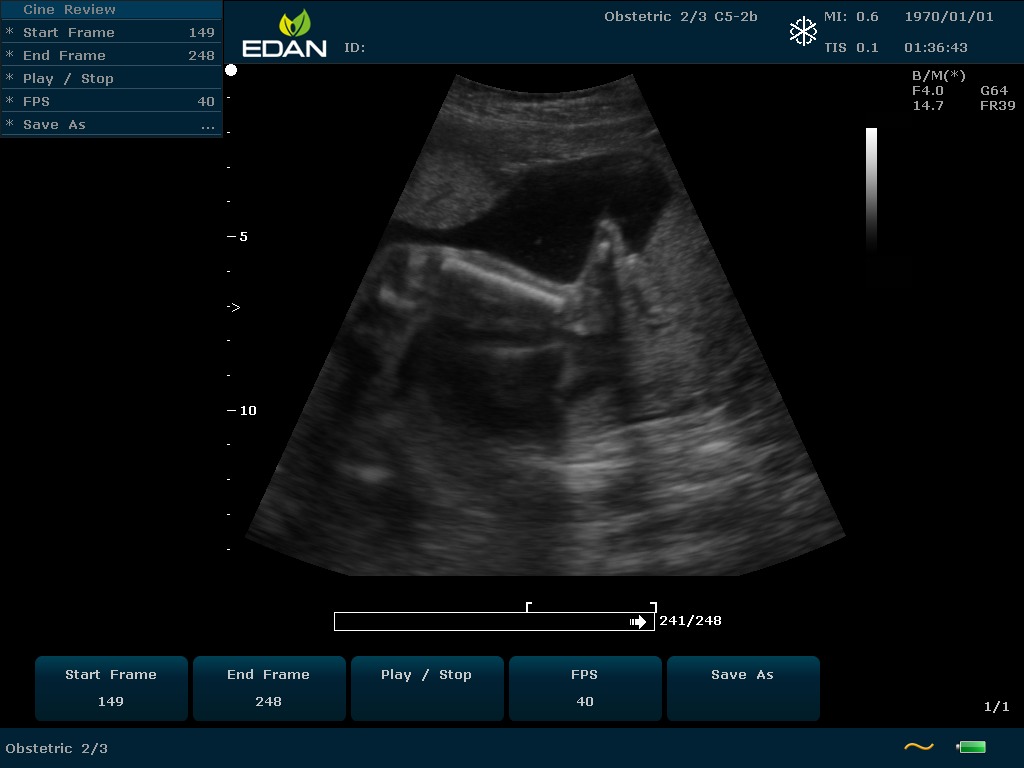

Портативный УЗИ-аппарат среднего класса U60 Edan c цветным допплером — универсальное устройство, удивляющее сочетанием компактности и многофункциональности.

Особенность U60 Edan — расширенное применение. Ультразвуковой аппарат рекомендован для абдоминальных исследований, гинекологии и акушерства, кардиологии, педиатрии, урологии, изучения малых органов, сосудов. Для U60 Edan используются конвексные, линейные, фазированные и внутриполостные датчики.

Передовые технологии позволяют повысить качество визуализации в несколько раз. УЗИ-аппарат U60 Edan отличается возможностью быстрой настройки визуализации. Специальные функции позволяют моментально отображать данные за счет быстрой оптимизации параметров. Режимы визуализации: B-mode, M-mode, Color Doppler, Power Doppler Imaging, Pulsed Wave Doppler, Continuous Doppler.